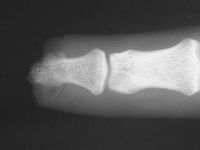

| Distal phalanx

fracture stabilization. Pins were placed to protrude

proximally in anticipation of flap cover. |